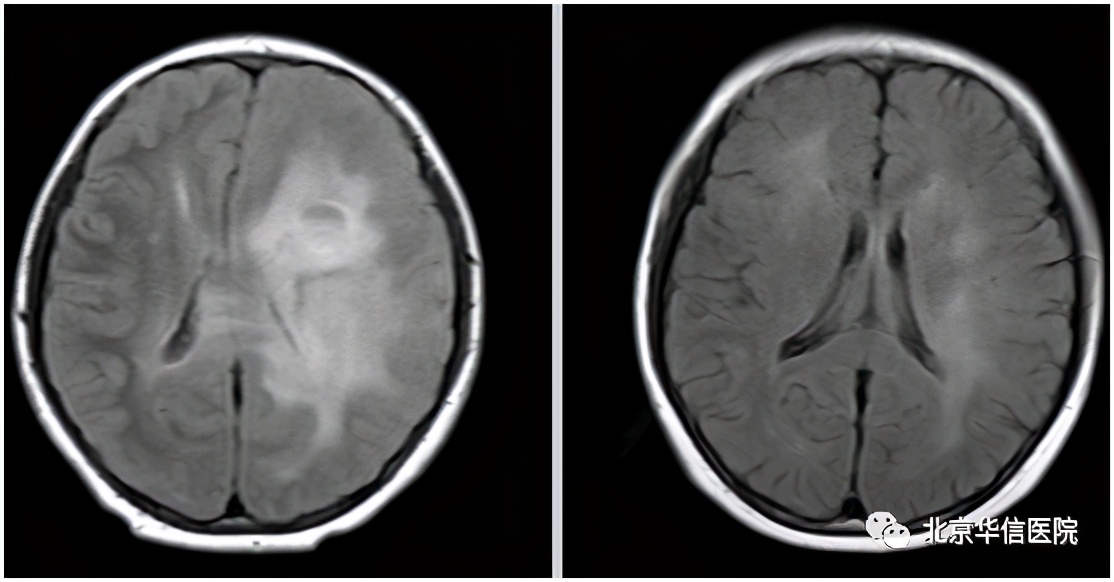

据文献资料显示,GC 患者预后极差,确诊后无进展生存期和中位总体生存期仅分别为10个月和13个月。另外,梅梅和常规的大脑胶质瘤患者病情还不太一样,她左侧额顶叶病变穿刺活检病理结果为小细胞胶质母细胞瘤(WHOⅣ级),恶性程度更高。现在距离确诊已经14个月了,局部病灶控制得非常好。此次复查还发现,梅梅左侧额顶叶高级别病变已经完全消失,这个治疗结果更加令人欣喜!

放疗前(左);放疗后(右)